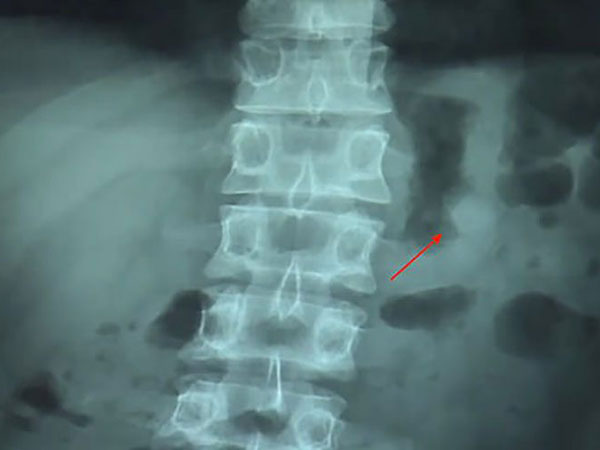

ಏರ್ ಪಾಡ್ ನ್ನು ನುಂಗಿದ ಪರಿಣಾಮ ಕ್ಸುಗೆ ಯಾವುದೇ ಸಮಸ್ಯೆಯಾಗಿರಲಿಲ್ಲ. ಆದರೆ ಆತನಿಗೆ ಚಿಂತೆಯಾಗಿತ್ತು ಎಂದು ಮಾಧ್ಯಮಗಳಿಗೆ ಹೇಳಿದ್ದಾನೆ. ಆತ ವೈದ್ಯರ ಬಳಿಗೆ ತೆರಳಿದ ಮತ್ತು ವೈದ್ಯರು ಎಕ್ಸ್ ರೇ ಮಾಡಿದರು ಮತ್ತು ಜೀರ್ಣಾಂಗ ವ್ಯವಸ್ಥೆಯಲ್ಲಿ ಏರ್ ಪಾಡ್ ಇದೆ ಎಂದು ಅವರು ಹೇಳಿದರು.